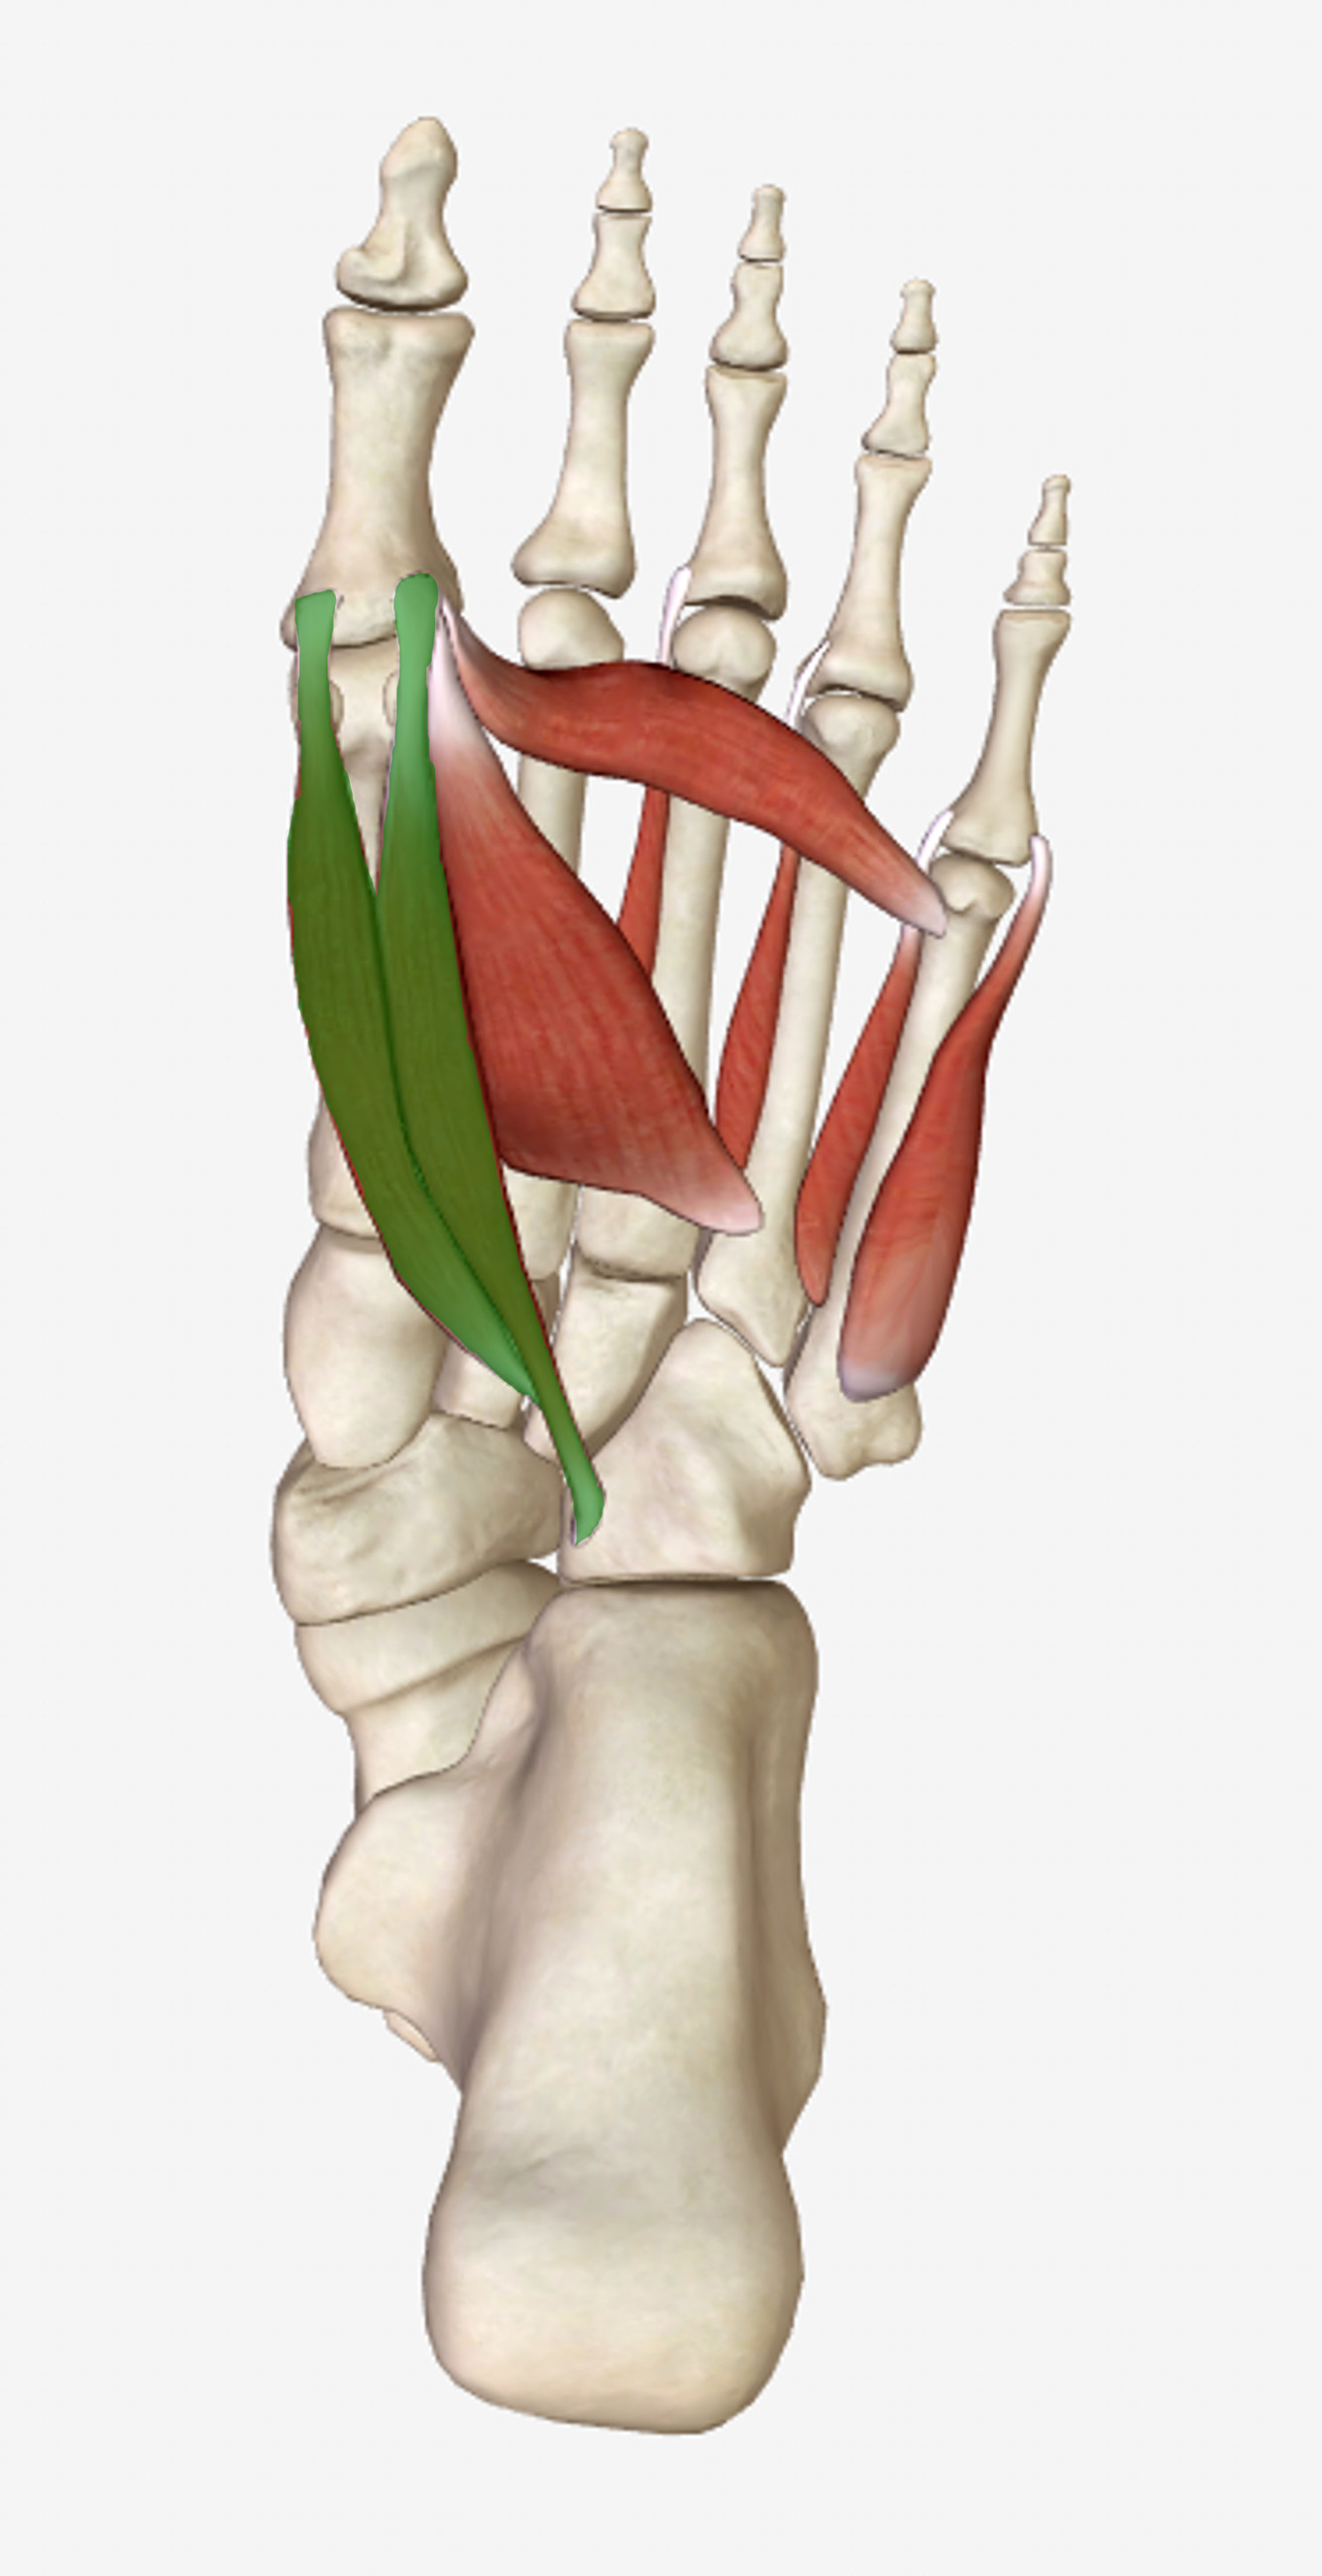

What is the innervation of this muscle?

Muscle - Extensor hallicus brevis

Deep fibular nerve

L5 + S1